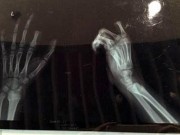

Bệnh nhân đang được điều trị tại Bệnh viện Đa khoa Trung ương Cần Thơ

Sau khi phát hiện vụ việc, K. được chuyển đến Bệnh viện Đa khoa Trung ương Cần Thơ nhưng bệnh nhân từ chối việc nối lại khớp. Qua tìm hiểu được biết, bệnh nhân này đã có vợ con, vào bệnh viện làm việc từ năm 2012.